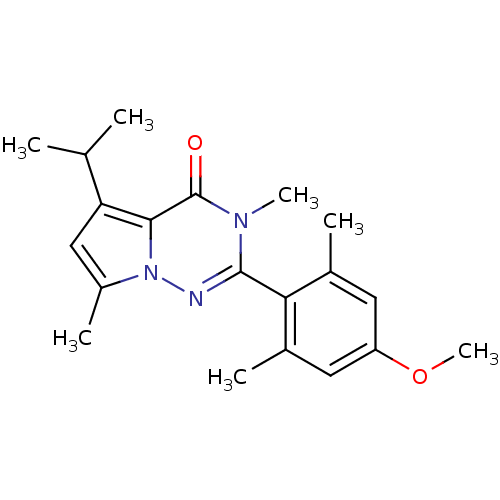

TargetCorticotropin-releasing factor receptor 1(Homo sapiens (Human))

Dupont Pharmaceuticals

Curated by ChEMBL

Dupont Pharmaceuticals

Curated by ChEMBL

Affinity DataEC50: 0.600nMAssay Description:Antagonist activity at human CRF1 receptor expressed in CHO-K1 cells assessed as CRF-stimulated cAMP accumulation by enzyme immunoassayMore data for this Ligand-Target Pair